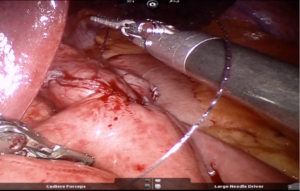

Using peri-gastric dissection, a small gastric pouch of capacity 20–30 mL is created. To start with, Phrenoesophageal membrane is divided using monopolar energy or ultrasonic shear while fundus of stomach is retracted caudally. Perigastric dissection is commenced by division of Gastrohepatic ligament between the first and second division of left gastric vessel and lesser sac is entered. It is done with the help of Harmonic scalpel in R1while stomach is being retracted laterally using R3. Care is taken to avoid injury to Vagus while entering lesser sac (Figures 5,6).

After delineating and entering lesser sac a 60-mm blue/tan cartridge is used by the surgeon on patient side to start division of stomach horizontally (Figures 7,8).